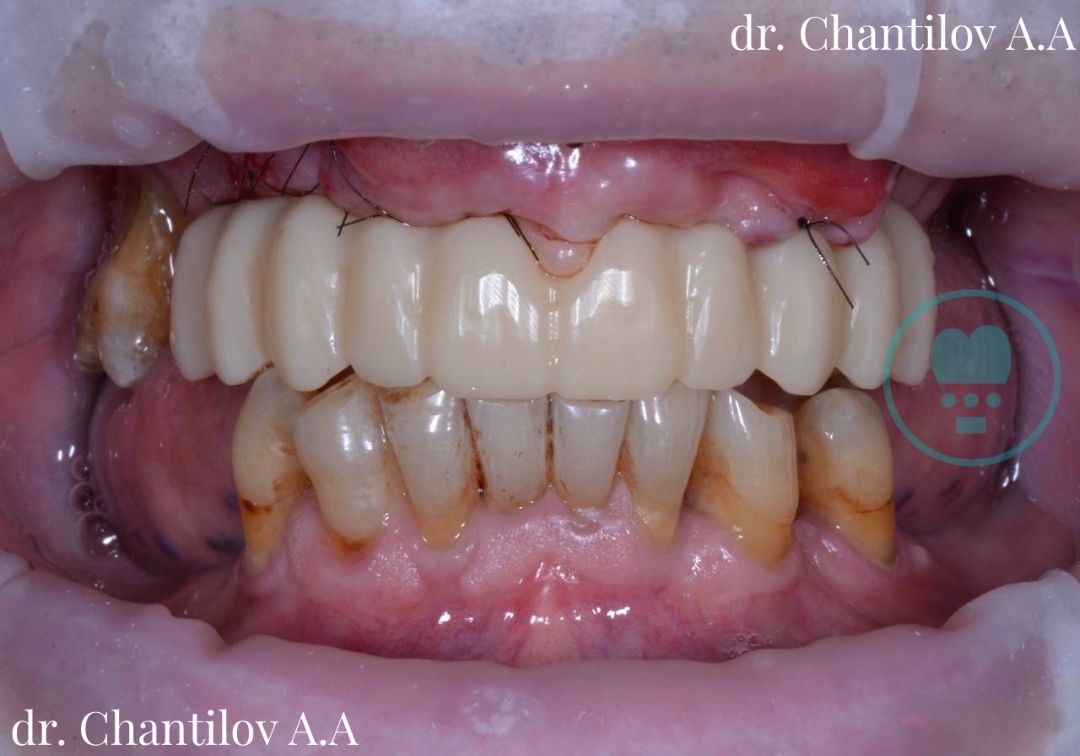

Имплантация зубов челюсти - фото до и после